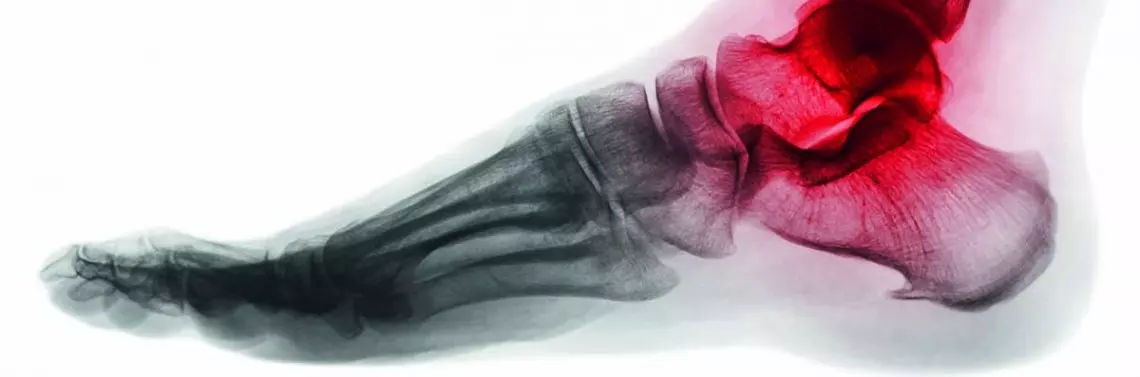

Na podeszwowej stronie stawu śródstopno-paliczkowego pierwszego (MTP I – hallux metatarsophaIangel) leżą dwie trzeszczki (ossa sesamoidea): boczna i przyśrodkowa (nazywane również odpowiednio trzeszczką strzałkową i piszczelową).

Trzeszczki leżą w bruzdach nasady dalszej I kości śródstopia. Ich powierzchnia grzbietowa jest pokryta chrząstką stawową, tworząc staw śródstopno-trzeszczkowy z I kością śródstopia. Od strony podeszwowej staw zamyka płytka podeszwowa (plantar plate), w skład której wchodzą: torebka stawowa, dystalny przyczep części włókien rozcięgna podeszwowego oraz ścięgno mięśnia zginacza krótkiego palucha.

• śródstopno-trzeszczkowe, biegnące od I kości śródstopia do trzeszczek [1–3] (zdj. 1).

Podczas chodu trzeszczki przyjmują ok. 40–60% obciążenia masy ciała, natomiast podczas biegu czy skoku obciążenie to wzrasta osiem razy [2]. Mięsień zginacz krótki palucha (flexor hallucis brevis, FHB) wraz z trzeszczkami bierze udział w fazie odbicia, nadając przyspieszenie niezbędne do przemieszczania się. Siła mięśnia jest zwiększona dzięki trzeszczkom, które oddalają ścięgno od osi stawu MTP I.